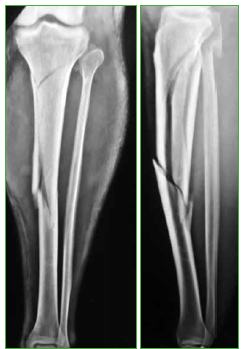

Todos fueron evaluados inicialmente con radiografias simples de frente y de perfil de la pierna, asi como con una tomografia computarizada (TC) de la articulacion de la rodilla o tobillo, segun el extremo de la tibia comprometido (Figura 1). Tres casos eran fracturas expuestas, que fueron tratadas de urgencia, con una limpieza quirurgica y estabilizacion inicial con fijador externo. Clasificamos las fracturas expuestas segun Gustilo-Anderson.9 Los datos demograficos y las caracteristicas de las fracturas se detallan en la Tabla.

Figura 1. Caso 11. Fractura de tibia 41A.3